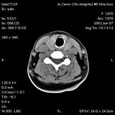

Диффузные изменения щитовидной железы с гиперплазией и очаговым процессом правой доли. Диффузные изменения щитовидной железы с гиперплазией и очаговым процессом правой доли

Пациент Р., 52 года

Диффузные изменения щитовидной железы с гиперплазией и очаговым процессом правой доли.

ЦКБ5 Южной железной дороги, отделение лучевой диагностики.

Щитовидная железа расположена обычно. Размеры: правая доля 38х23х66 мм, левая доля 31 15х36 мм. Плотность железы 80-95 HU. Структура неоднородна. В правой доле участок пониженной плотности (55 HU) размерами 23х15х30 мм с нечеткими контурами.

Нижний полюс правой доли на уровне верхнего края рукоятки грудины. Трахея слегка смещена влево, просвет ее не изменен. Костно-деструктивные изменения не определяются. Лимфоузлы шейной локализации не изменены.